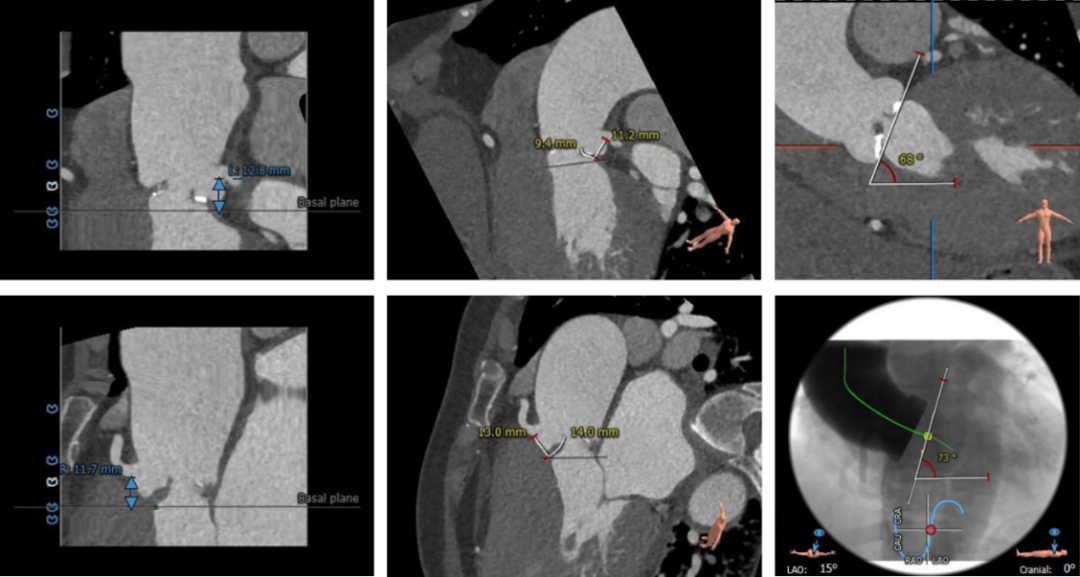

术前CT评估

CT结果显示:

• 三叶式主动脉瓣,瓣叶轻中度钙化,钙化分布欠均匀,主要分布在瓣叶边缘及管壁附着缘,瓣叶严重增厚,局部交接粘连

• 左右冠开口高度尚可,未见明显冗长瓣叶

• 流入端形态呈直桶状,瓦氏窦、窦管交界内径偏大,升主动脉瘤样扩张

• 左室腔内径可,心室壁增厚

• 主动脉瓣环与水平面夹角近70°,横位心,主动脉弓角度与宽度可

• 入路血管散在钙化,双侧血管内径良好,整体入路血管条件良好